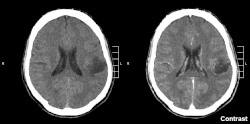

Glioma in the left parietal lobe (brain CT scan), WHO grade 2 | |